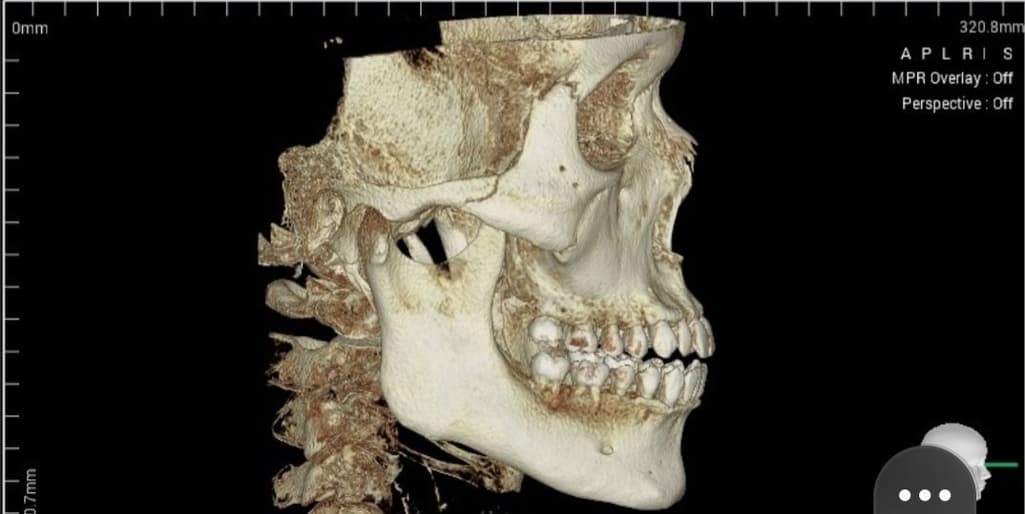

구강악외과에서 턱정밀상담 결과 하관평균길이가 성인남성평균보다 길고 돌출되었다고 들은 이후에 신경이 쓰여 수술 질문좀 하고싶습니다

실제와 사진은 다르겠지만 ct와사진만보고 개인적은 의견 적어주시면 참고하도록 하겠습니다

현재는 수술이 필요할 정도로 하악이 돌출되거나 발달하지는 않았습니다.

지극히 일반적인 턱으로 억지로 턱을 넣을 경우에 이에 따른 부작용도 생각해야 하며

수술로 인해 오히려 소하악증이나 코골이 등의 문제가 생길 수 있어 자연 그대로가

가장 안전할 수 있습니다. 감사합니다.